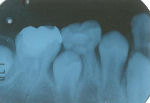

右下6番虫歯になりました。

右下6番の虫歯がかなり大きくなっていました(一枚目写真)。軟化象牙質を全て取ってしまうと歯髄に達してしまうのでindirect pulp cappingを行いました。一年後には歯髄の側に第二象牙質ができています(二枚目写真)。その後軟化象牙質を完全に取り去りインレーで修復しました(三枚目写真)。6番目の歯は永久歯の中でも一番虫歯になりやすい歯ですが、小学3年生の段階で神経がなくなると一生は持ちません。なるべく神経を残すことができるようにこういった治療もあるのです。